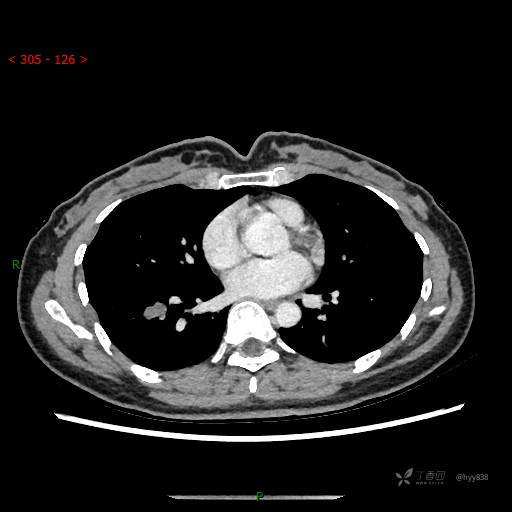

胸部CT平扫